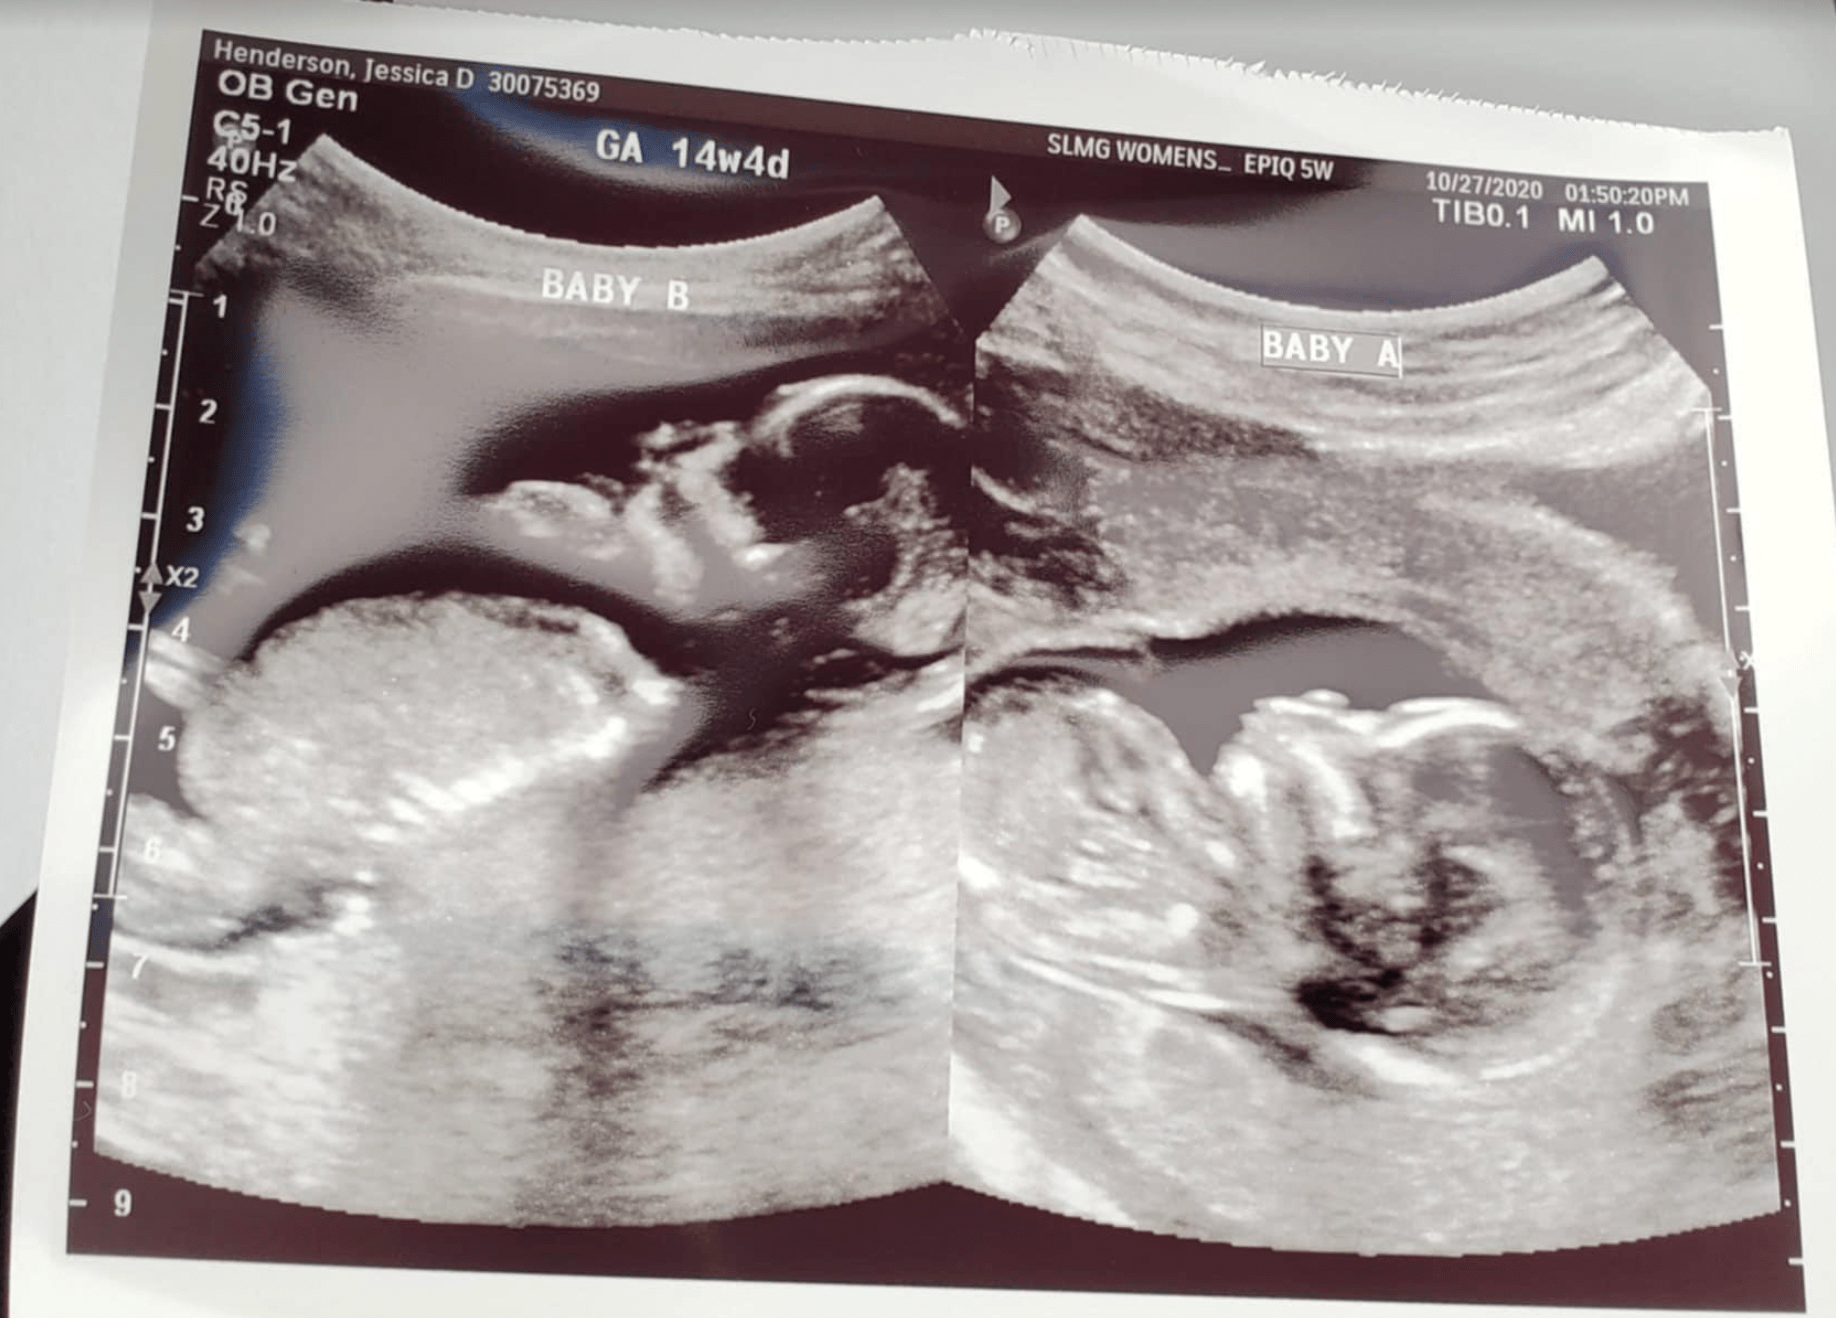

Their first embryo transfer resulted in a twin pregnancy but sadly ended in miscarriage due to a newly discovered blood clotting disorder. This disorder was treatable with daily blood thinner injections. Faced with three remaining embryos, Jessie and Stephen decided to transfer all three, hoping to conclude their journey. This final transfer resulted in a healthy pregnancy with twins. The twins were born at 35 weeks and required a three-week NICU stay. Stephen’s supportive commander allowed him to be present during this critical time, ensuring family support.